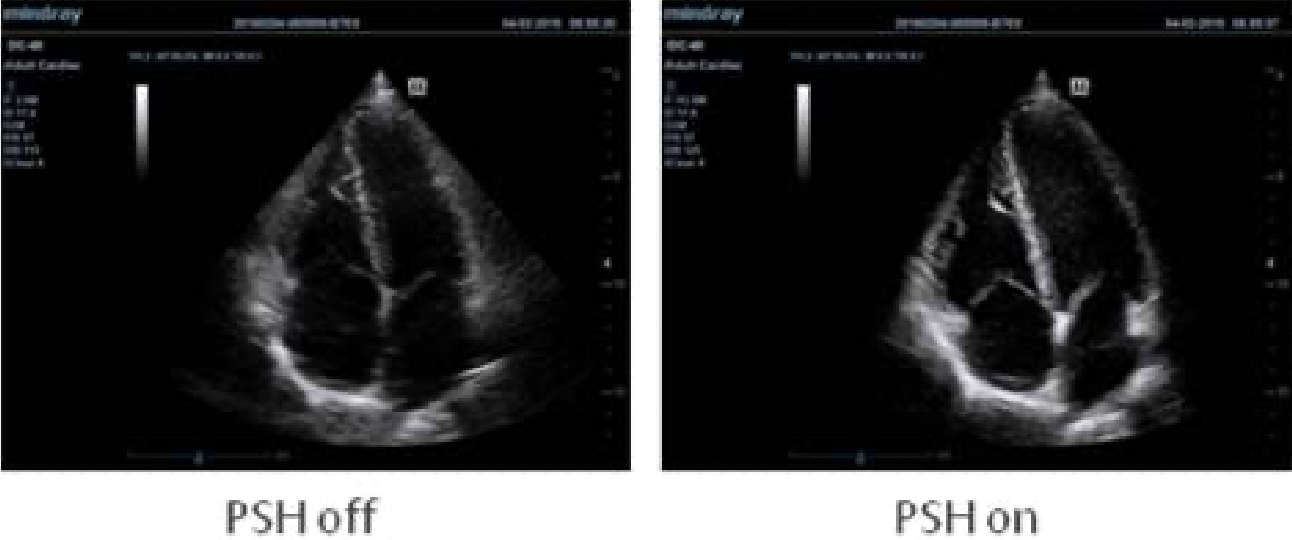

Benefitting from technology migrated from established ultrasound systems, the DC-40 guarantees exceptional image quality. Powered by imaging technologies including iClear, iBeam, PSH and the wide range transducer family, the DC-40 is a practical machine for confident scanning.